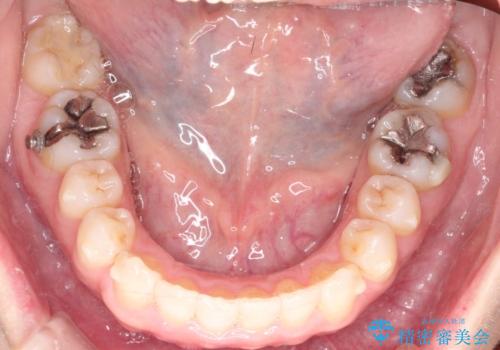

【インビザライン 】前歯のガタガタを治したい

- 前歯のガタガタを主訴に来院されました。

インビザライン で治療しました。途中は使用時間が20時間を切ることもありましたが、それでも頑張って使っていただき1年半で矯正終了することができました。